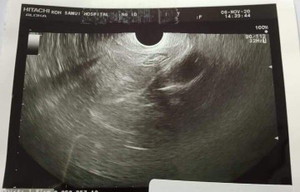

ตั้งครรภ์ประมาณ5w6d มีเลือดออกไม่ปวดท้องหมอตรวจปากมดลูกปิดอัลตร้าซาวด์ผ่านช่องคลอดหมอให้กลับบ้านได้

ภาพอัลตร้าซาวด์ดูเห็นตัวอ่อนยังค่ะดูยังไง